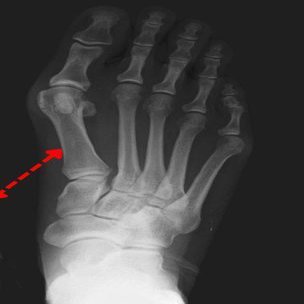

▼ 過回内が起こるとどうなるか?

土踏まずが低下し内側アーチが潰れる(扁平足)

距骨が内側・前方へ滑り込み足部が内に倒れ込む

中足骨(とくに第 1 中足骨)が内側へ逃げる

結果として母趾が外側へ押し出される(外反角増大)